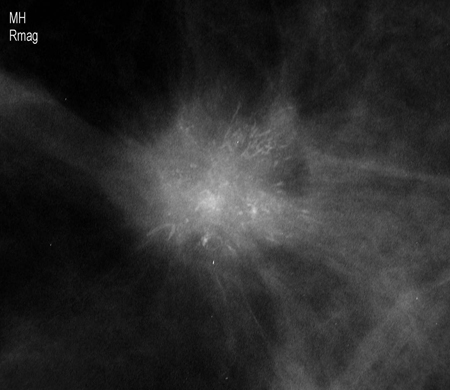

[Figure caption and citation for the preceding image starts]: Mamografía de cribado en la que se observa una masa en la mamaCortesía de la Dra. Nancy Pile, University of Louisville; utilizada con autorización [Citation ends].

[Figure caption and citation for the preceding image starts]: Imagen aumentada en la que se observa una masa espiculada irregular con calcificaciones asociadasCortesía de la Dra. Nancy Pile, University of Louisville; utilizada con autorización [Citation ends].